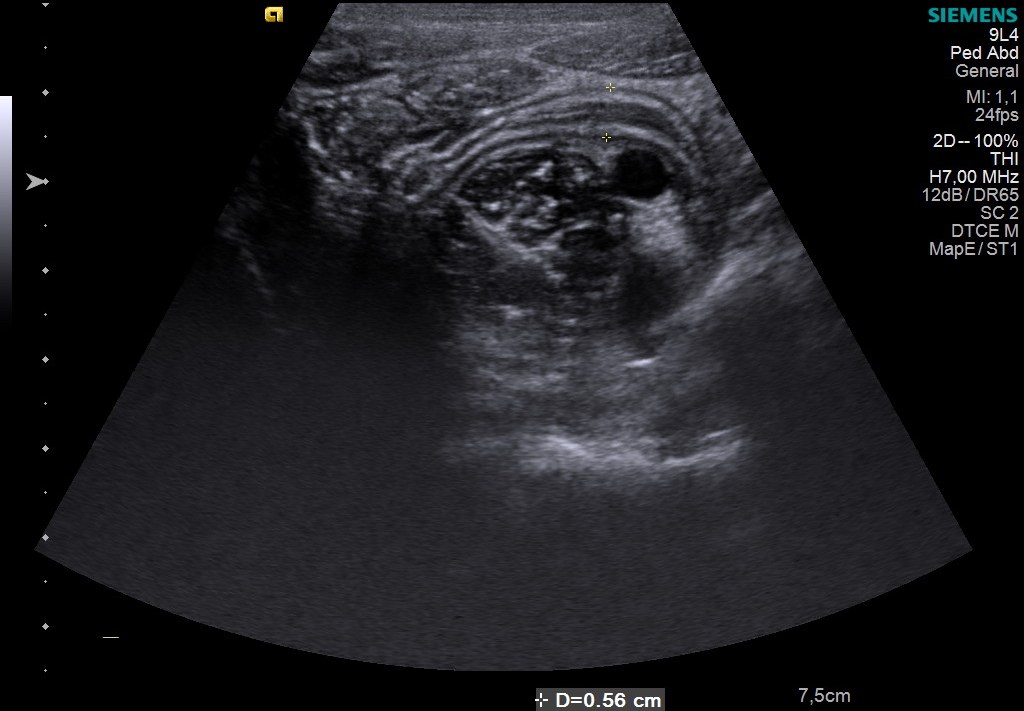

A young male patient presented to the ER with acute onset of pain in the right lower quadrant. Ultrasound examination has been performed and it suggested the following diagnosis of…?

Case courtesy of Dana Nedelcu MD